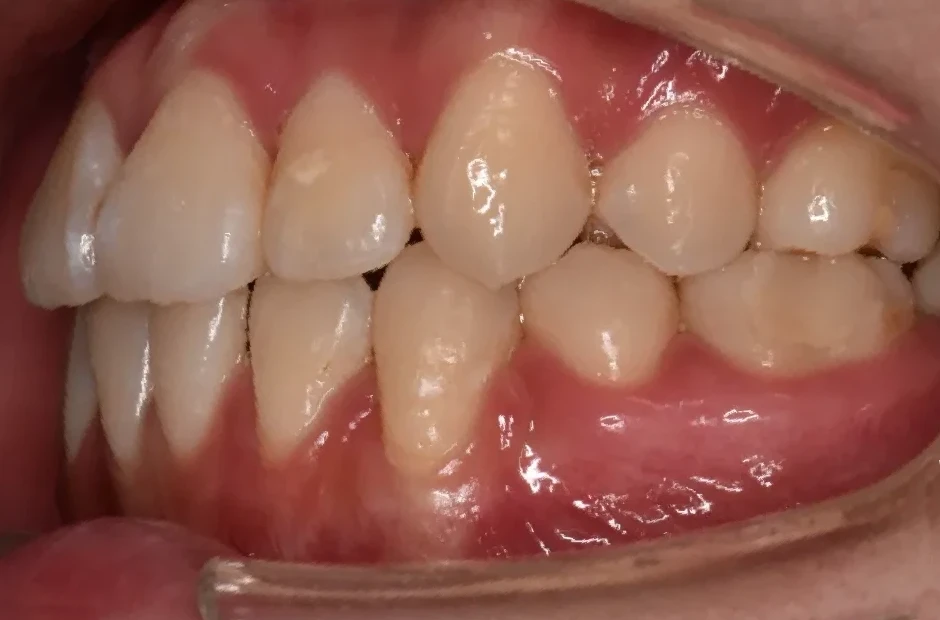

叢生

| 診断名・主訴 | 叢生 |

|---|---|

| 年齢・性別 | 43歳・女性 |

| 治療期間・回数 | 2年7か月 27回 |

| 治療に用いた主な装置 | 舌側矯正 |

| 抜歯部位 | 両顎4,4 |

| 治療費 | 100万円(税抜) |

| リスク・副作用 | 装置による違和感・疼痛・歯肉退縮・歯根吸収・虫歯のリスクなど |

治療前